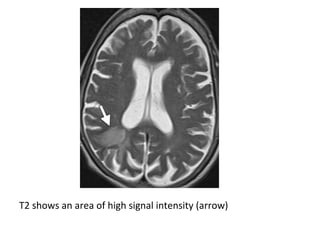

T1 shows an area of low signal intensity (arrow)

T2 shows an area of high signal intensity (arrow)